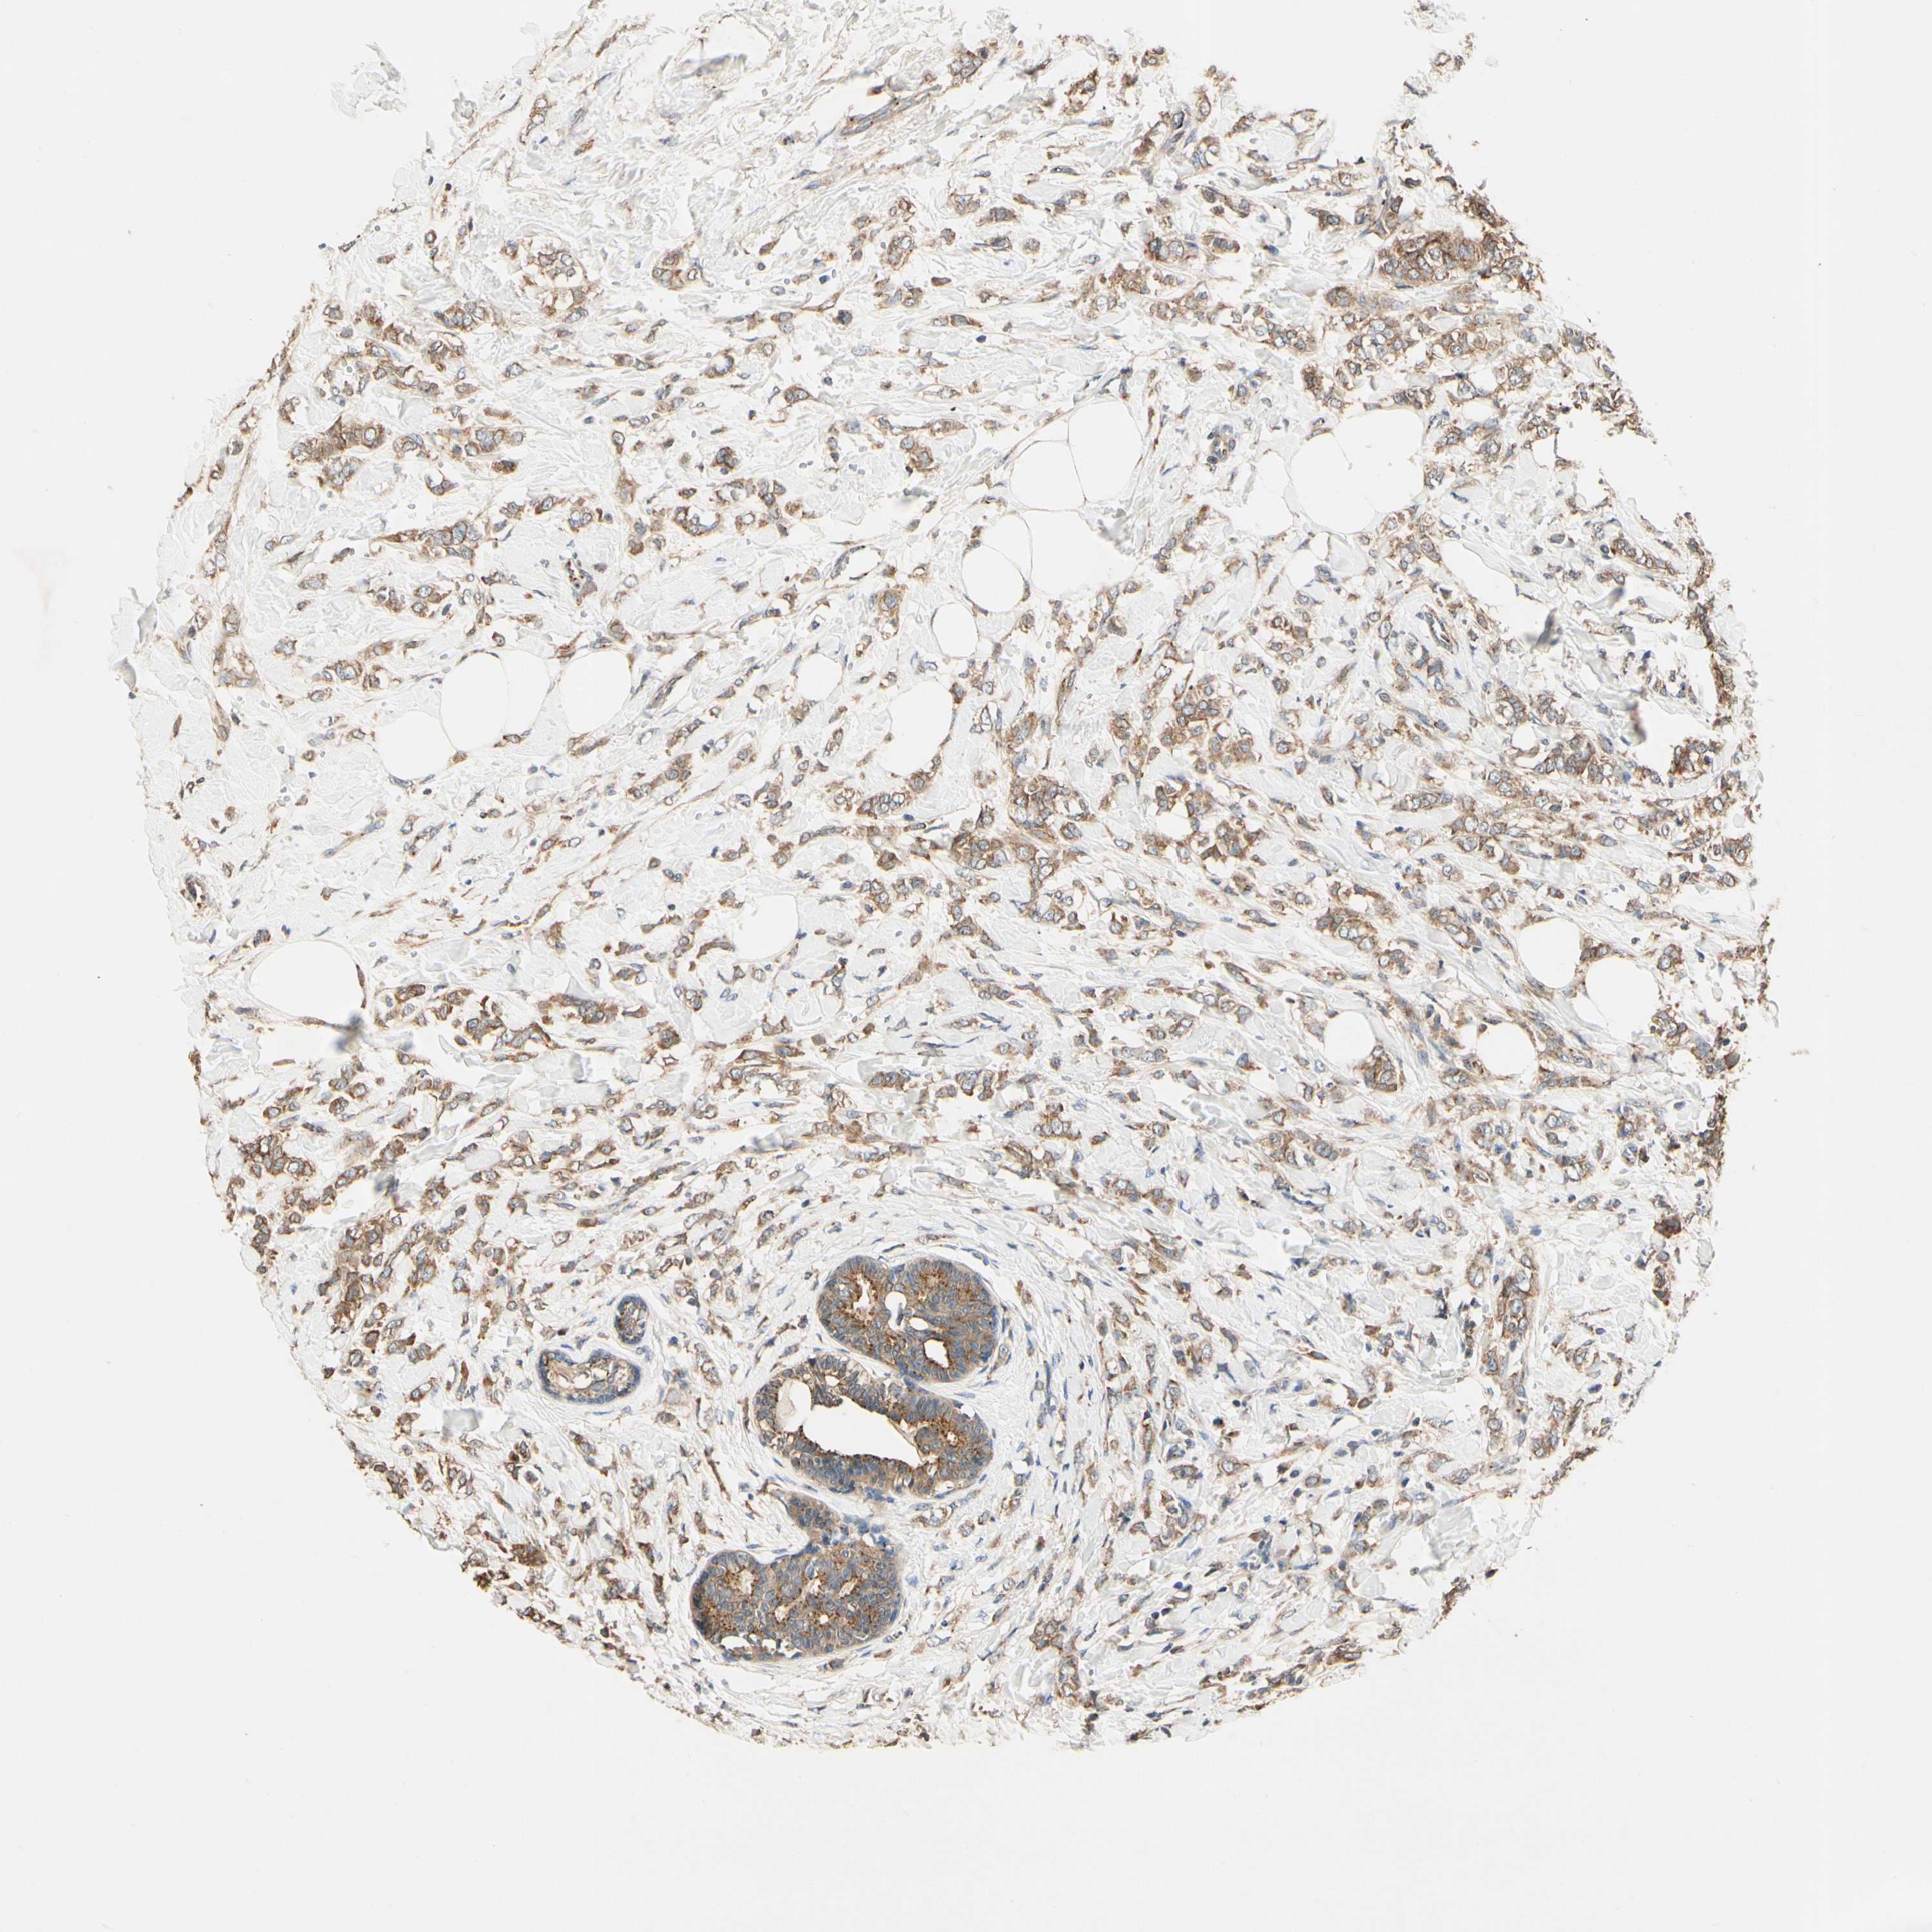

BRCA TCGA BRCA VALIDATION PROTEIN EXPRESSION

ANTIBODIES

AND

VALIDATION